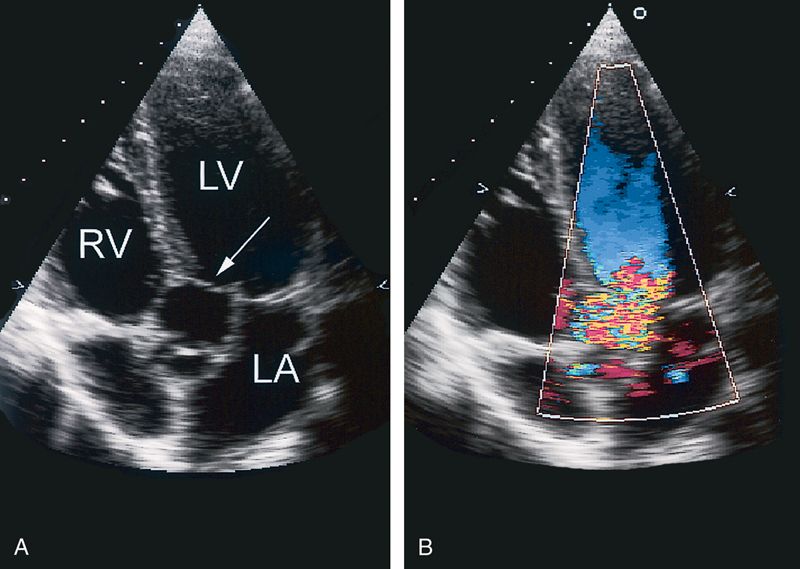

فحوصات تشخيصية لبعض امراض القلب والشرايين التاجية